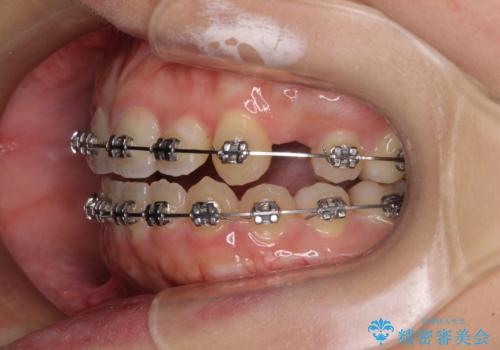

- 矯正装置

- メタルブラケット

- 八重歯と上下前歯のでこぼこを気にして来院された患者様です。

上下前歯部叢生のスペース獲得のため、上下顎左右小臼歯各1歯(計4本)と全ての親知らずを抜歯して、矯正治療を行うこととしました。